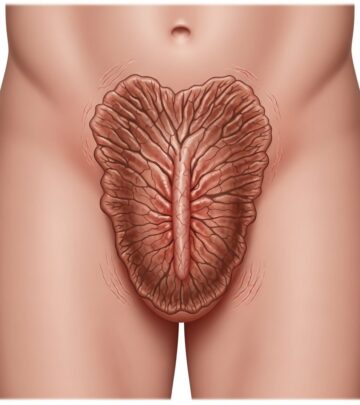

Microscopically, fibrosarcoma displays poorly circumscribed infiltrative growth of uniform spindle cells arranged in long sweeping fascicles with a characteristic herringbone pattern, reminiscent of skeletal muscle. Cells have elongated nuclei with tapered ends, scant cytoplasm, and minimal pleomorphism in low-grade forms. Collagen bands separate fascicles. Mitotic activity varies (5–20/10 HPF), with atypical forms in high-grade tumours. Necrosis is focal; myxoid change or giant cells may occur. Infantile variants show higher cellularity and mitoses but behave indolently. Fibrosarcomatous transformation in DFSP (10–20% cases) features higher-grade herringbone areas with necrosis and increased mitoses (>10/10 HPF).

The tumour permeates dermis and subcutis in a lattice-like pattern, sparing epidermis. Deep extension to fascia/muscle is common in recurrences. Grading relies on mitotic rate, necrosis, and pleomorphism: low-grade (<5 mitoses/10 HPF, no necrosis); high-grade (>10 mitoses/10 HPF, necrosis present).